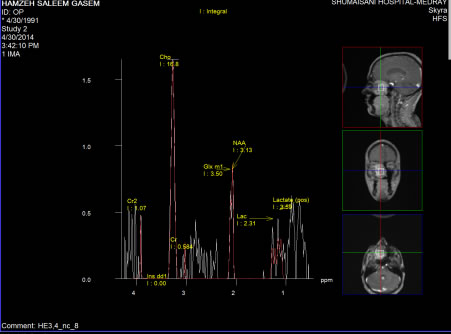

03-MAY-2014  HAMZEH SALEEM QASEM 23 YEARS CHORDOMA OF THE RIGHT MAXILLO-SPHENOIDAL AREA WITH SECONDARY EXOPHTHALMUS.

The patient came to the clinic 29-April-2014 complaining of difficult breathing fro the right nostril with progressive exophthalmus right eye for one year. He was operated for septal deviation elsewhere without benefit. CT-scan done 29-April-2014 showing a huge mass in the right maxillo- sphenoidal area, pushing the septum to the left and elevating the medial wall of the right orbit up and lateral.

The patient was sent for MRI investigations with contrast with MRA of the brain and carotid systems. There was no arterial involvement and the mass was totally extracranial, but reaching and abutting the pituitary floor and shifting the right optic nerve medially.

Through the right nostril, the tumor was attacked and piece-meal resection was performed. Fresh frozen biopsy telling that it is either meningioma or fibrous dysplasia. Inspection of the tumor bed cavity was negative. Intraoperative MRI done showing huge remnant of the tumor, which was followed and resected. Hemostasis. 2 nasal tubes were inserted.

The patient is not characteristic for either meningioma, nor for fibrous dysplasia. It is benign and grossly looking as chordoma.